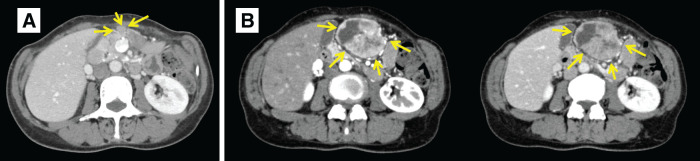

Case presentation: At the age of 44, a 60-year-old female underwent a laparoscopic-assisted proximal gastrectomy for gastric cancer at a previous hospital. Neuroendocrine carcinoma was diagnosed following a postoperative pathological examination based on histological findings and immunostaining results. The patient was followed up without any recurrences. After 14 years, a follow-up contrast-enhanced CT revealed a 9-mm mass on the greater curvature side of the gastric antrum, which was suspected to be lymph node swelling at the previous hospital. After 8 months, she came to our hospital with abdominal discomfort and distention. The CT scan revealed a 55-mm mass, indicating an increase in the previously mentioned mass. At our hospital, the patient underwent open tumor resection. The pathological findings revealed a recurrence of gastric NEC. The patient has been recurrence-free for 6 months following surgery.